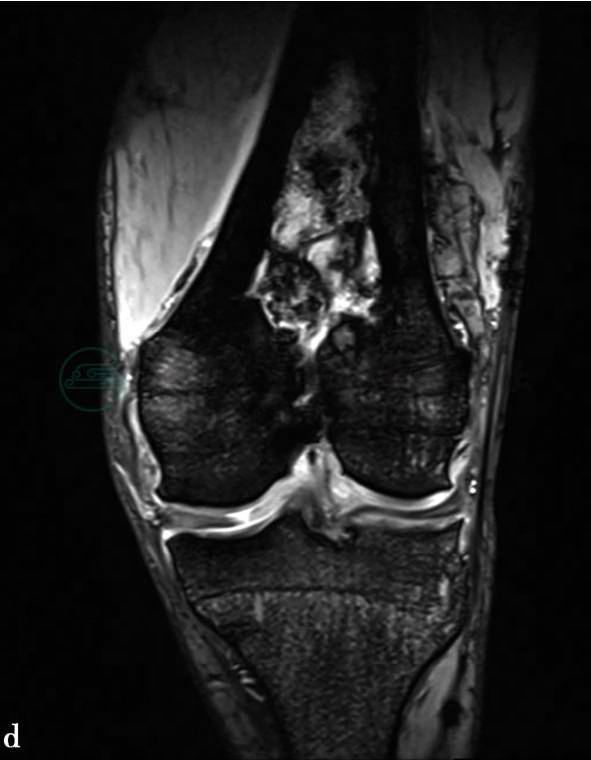

(3)病例6:

CT平扫及MRI平扫。

图3 图3a、e、f,CT平扫示左股骨中下段骨皮质不规则增厚,骨髓腔变窄,其后方骨皮质局部缺损,相邻软组织肿胀。骨髓腔内可见大片状溶骨性破坏及骨质硬化。图3b~d,MRI平扫示左股骨中下段骨皮质不均匀增厚,后侧有一缺损。图3b,T1WI上呈低信号。图3c,T2WI脂肪抑制像上呈高信号,信号不均匀。骨髓腔内病灶通过后侧缺损的骨皮质向后侧软组织延伸,致大腿后侧软组织广泛肿胀